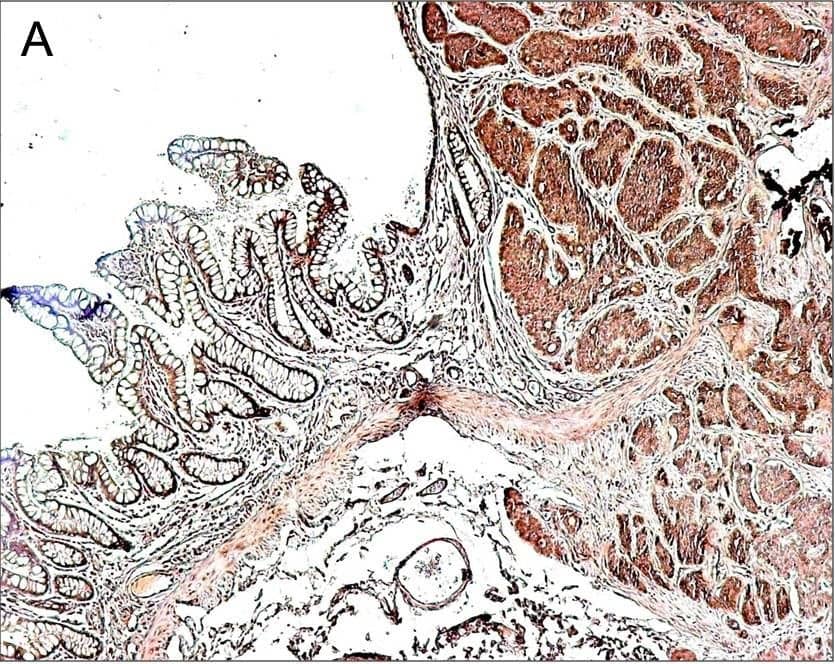

Immunostaining of neuroendocrine tumors. Representative photomicrographs demonstrating anti-connective tissue growth factor (CCN2) (panel A) immunostaining of gut carcinoid tumor tissue. CCN2 immunoreactivity was seen in cells corresponding to chromogranin A-positive tumor cells and gut smooth muscle (denoted by arrows in panels B and C, respectively). All sections were counterstained with hematoxylin. Magnification ×50. Image collected and cropped by CiteAb from the following publication (https://pubmed.ncbi.nlm.nih.gov/20053285), licensed under a CC-BY license. Not internally tested by R&D Systems.

CTGF/CCN2 antibody in Human Breast Cancer Tissue by Immunohistochemistry (IHC-P).

CTGF/CCN2 was detected in immersion fixed paraffin-embedded sections of human breast cancer tissue using 25 µg/mL Human CTGF/CCN2 C-Terminus Monoclonal Antibody (Catalog # MAB660) overnight at 4 °C. Tissue was stained with the Anti-Mouse HRP-DAB Cell & Tissue Staining Kit (brown; Catalog # CTS002) and counterstained with hematoxylin (blue). View our protocol for Chromogenic IHC Staining of Paraffin-embedded Tissue Sections.